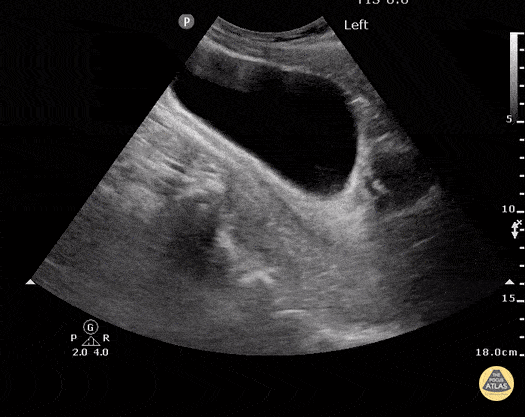

No free fluid is seen behind the bladder in this sagital view. Dr. Justin Bowra